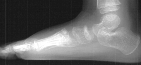

Radiographs of the patient were obtained on her presentation to our clinic. These confirmed the finding of increased radiodensity of the navicular with a flattened appearance to the ossific nucleus. Furthermore they revealed increased density and callus formation in the proximal 1st through 4th metatarsals. This was consistent with multiple non-displaced fractures of the proximal metatarsals secondary to trauma. While Kohler's disease cannot be ruled out in this case, it is more likely that the patient had symptoms produced by her metatarsal fractures. The radiographic appearance of the tarsal navicular almost certainly preceded the acute traumatic event. Therefore, she probably had metatarsal fractures superimposed on irregular ossification of the tarsal navicular giving a clinical picture similar to Kohler's disease.